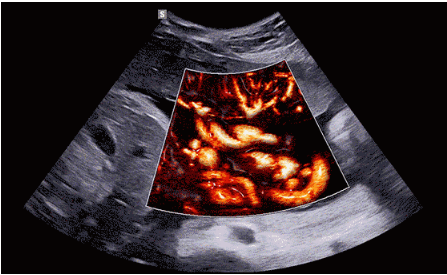

CrystalLive?是三星最新的超聲成像引擎,同時增強了2D圖像處理能力、3D渲染能力和彩色信號處理能力,能夠在復(fù)雜情況下提供出色的圖像性能,具備檢測外周血管、微循環(huán)血流的能力。

3D/4D成像方面,Hera i 10通過結(jié)合先進的圖像渲染技術(shù),著重加強了邊緣和小結(jié)構(gòu)的可視化能力。